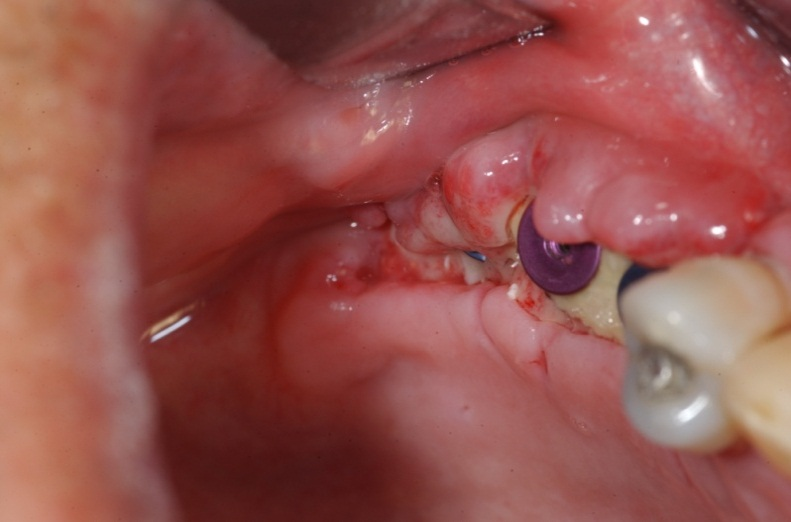

Bạn đã thực sự tìm hiểu kĩ về chân răng nhân tạo trước khi thực hiện cấy ghép? Trong bài viết này chúng tôi muốn cung cấp cho các bạn thông tin về “Những biến chứng và thất bại của cấy ghép implant”. Khi nền y tế càng phát triển thì thông tin càng được đưa đa chiều, để bệnh nhân hiểu được đa góc cạnh và chuẩn bị tâm lý tốt hơn. Việc chỉ đưa thành công, ưu điểm thì có thể khiến bệnh nhân không nắm rõ để chuẩn bị đủ tâm lý dẫn đến những quyết định chấp nhận điều trị sai lầm.

Khi nền y tế càng phát triển thì thông tin càng được đưa đa chiều, để bệnh nhân hiểu được đa góc cạnh và chuẩn bị tâm lý tốt hơn. Việc chỉ đưa những thành công, ưu điểm thì có thể khiến bệnh nhân không nắm rõ để chuẩn bị đủ tâm lý dẫn đến những quyết định chấp nhận điều trị sai lầm.

Cắm implant là một phương pháp phục hình răng đòi hỏi kỹ thuật, trình độ cao, vì vậy bác sĩ cần có chuyên môn và giàu kinh nghiệm. Trong đó việc chẩn đoán chính xác ban đầu là bước không thể thiếu.

Cắm chân răng nhân tạo implant là một phương pháp trồng răng sứ hiện tại nhất hiện nay và đòi hỏi kĩ thuật thực hiện và quá trình chăm sóc hậu phẫu khá nghiêm ngặt và phức tạp. Nếu không thực hiện đúng kĩ thuật và chăm sóc tốt thì bệnh nhân rất có thể sẽ gặp phải những biến chứng sau khi trồng răng nhân tạo implant.